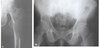

# Princípios básicos de tumores ósseos - Com base na imagem, classifique de acordo com Enneking:

- **B1 → latente** (*presença de esclerose*)

33

- **B2 → ativo** (*afila a cortical*)

34

- **B3 → agressivo** (*rompe a cortical*)